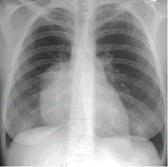

问题 女,18岁,自感胸闷,X光检查见纵隔占位,CT检查如图,最可能的诊断为 ( )

选项 A.纵隔畸胎瘤 B.上纵隔胸腺瘤 C.胸内甲状腺瘤 D.淋巴瘤 E.下纵隔胸腺瘤

答案 A